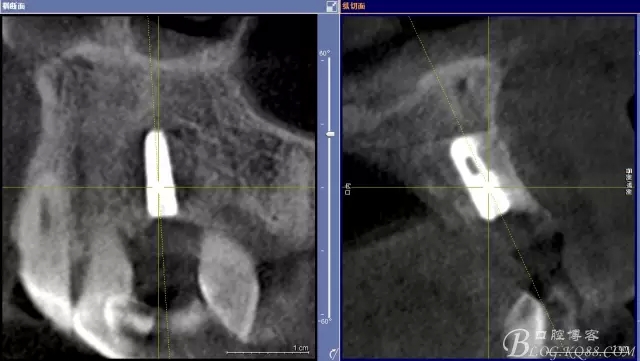

患者、楊xx、男、49歲。主訴:左側(cè)前牙拔除半年,活動(dòng)義齒修復(fù)四個(gè)月,要求種植修復(fù)。??茩z查:21缺失,牙槽粘膜厚度正常。CBCT檢查:高度16mm,寬度7mm.術(shù)前簽知情同意書。

圖1.術(shù)前的CBCT檢查:22缺失。

圖2.CBCT的三維成像及縱剖面、水平面影像

圖11.術(shù)后的CBCT檢查: